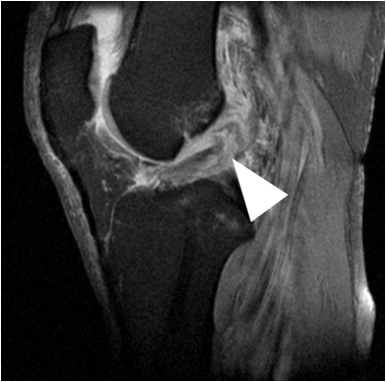

Fig. 6. Patient with knee trauma. Plain films reveal significant suprapatellar joint effusion (white arrows). A fracture is not seen. MR imaging reveals a torn anterior cruciate ligament (white arrow head).